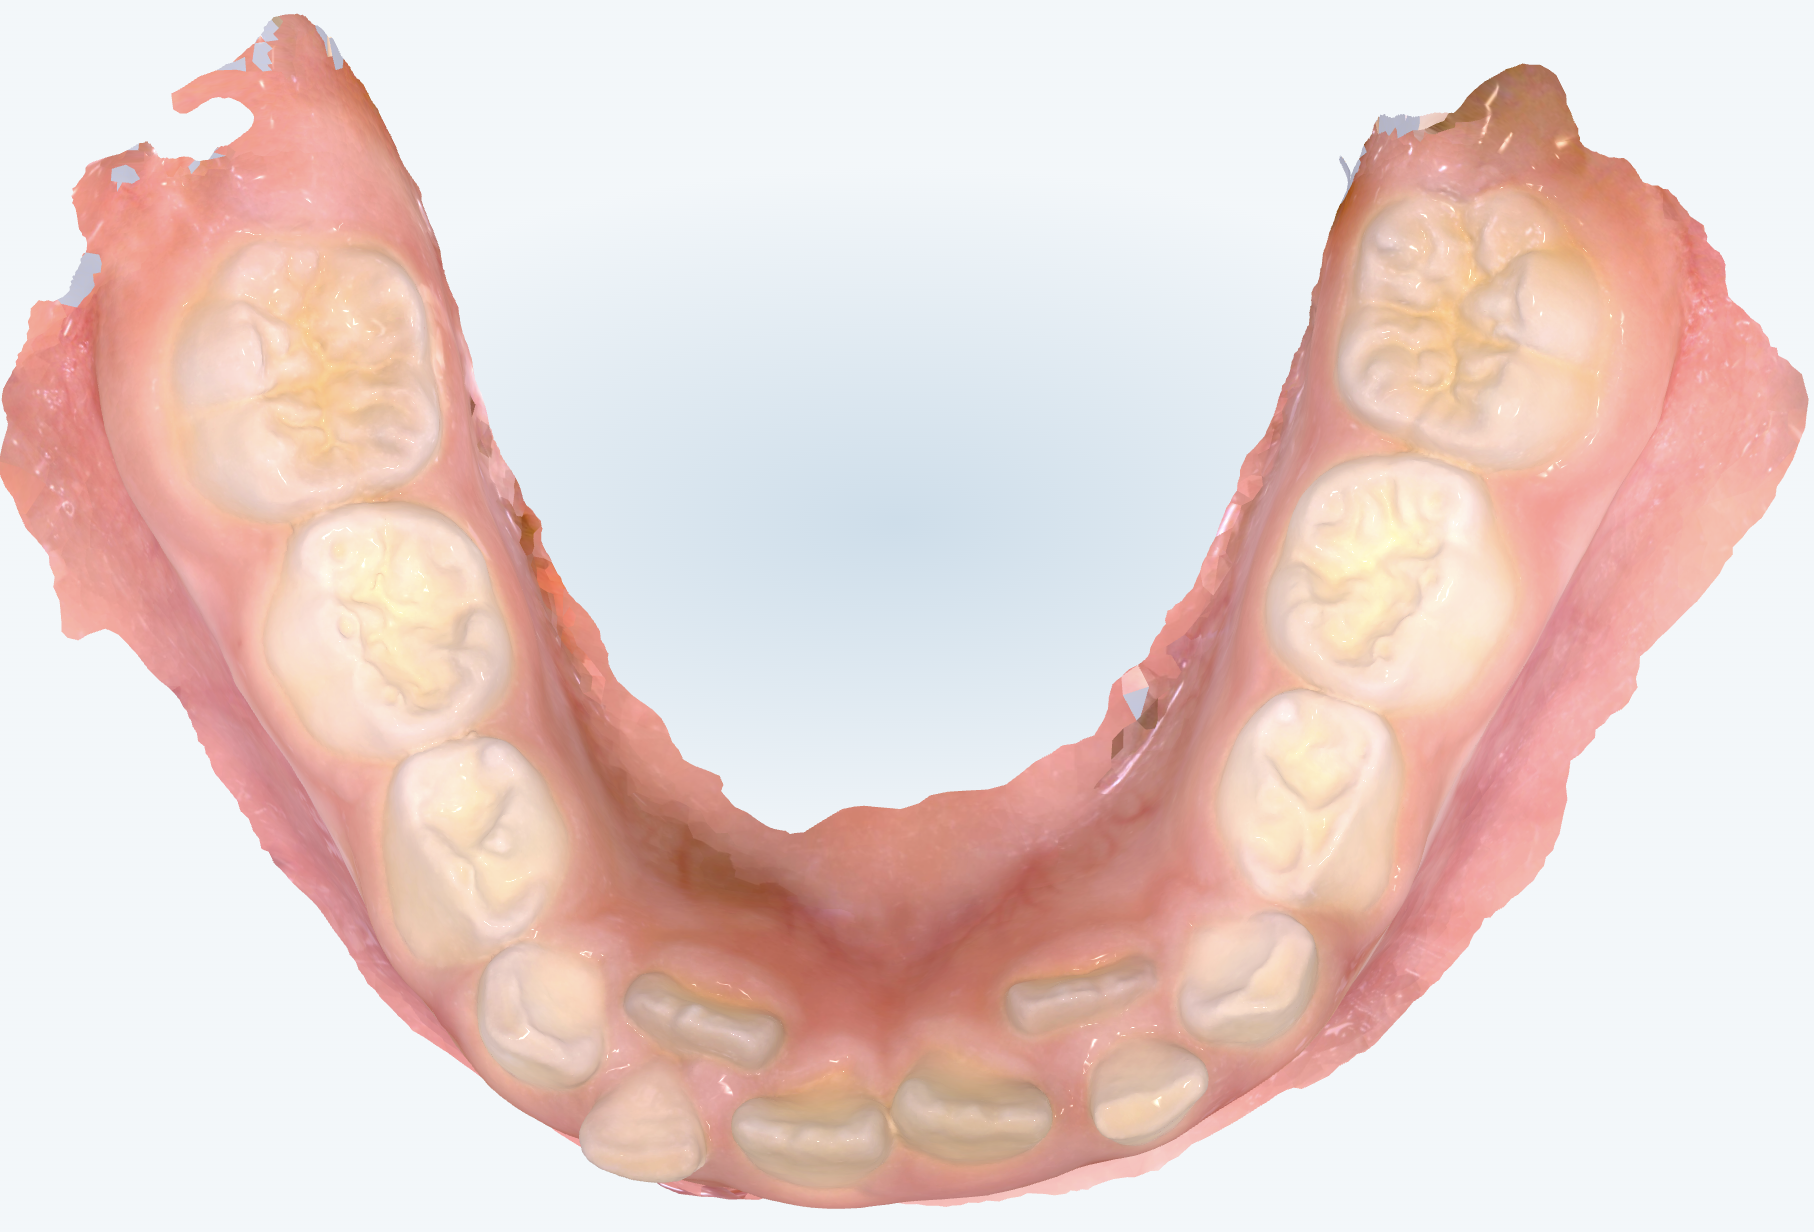

初診時の画像診断

永久歯の前歯が反対咬合になっていました。

下の前歯は乳歯の後ろから永久歯が生えてきて、2枚歯のようになっています。

そうですね、実際にレントゲンで確認してみたところ、乳歯の根の部分がかなり溶けていました。通常であれば、下から永久歯が押し上げてきて自然と乳歯が抜けるのですが、前後の位置関係がずれているために歯の根っこの吸収がうまくいっていなかったようです。